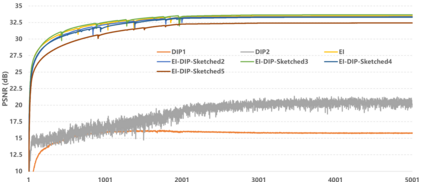

Equivariant Imaging (EI) regularization has become the de-facto technique for unsupervised training of deep imaging networks, without any need of ground-truth data. Observing that the EI-based unsupervised training paradigm currently has significant computational redundancy leading to inefficiency in high-dimensional applications, we propose a sketched EI regularization which leverages the randomized sketching techniques for acceleration. We then extend our sketched EI regularization to develop an accelerated deep internal learning framework -- Sketched Equivariant Deep Image Prior (Sk.EI-DIP), which can be efficiently applied for single-image and task-adapted reconstruction. Our numerical study on X-ray CT image reconstruction tasks demonstrate that our approach can achieve order-of-magnitude computational acceleration over standard EI-based counterpart in single-input setting, and network adaptation at test time.